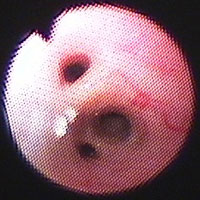

気管支鏡検査:第7病日に行った。肉眼所見で、左右主気管支内に白色円柱状物が多数みられた(図2)。ブラシ擦過細胞診にて、気管支粘膜上皮細胞、好酸球、杯細胞がみられた(図3)。気管支肺胞洗浄液(BAL)[RB2, 10ml×3, 回収率90%]にて総細胞数の軽度増加(421/μl)、好酸球数の増加(26.75%)がみられた。BAL液の培養にて細菌も真菌も検出されなかった。

図2 症例1の気管支鏡検査所見。左右主気管支内に白色円柱状物が多数みられた。